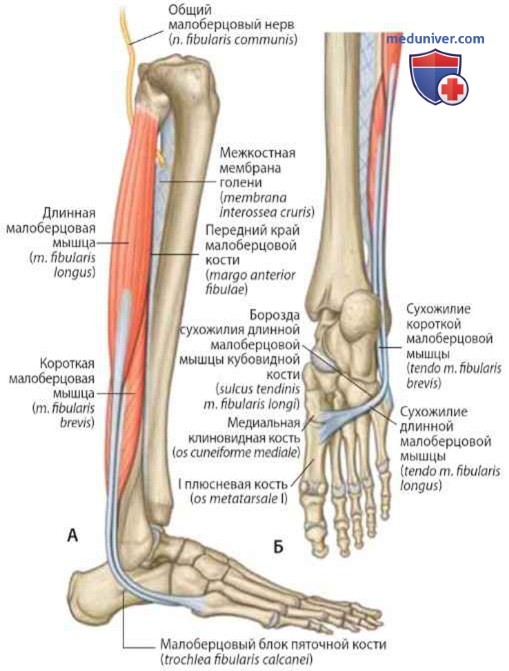

Анатомия подошвенной мышцы голени: подробное рассмотрение